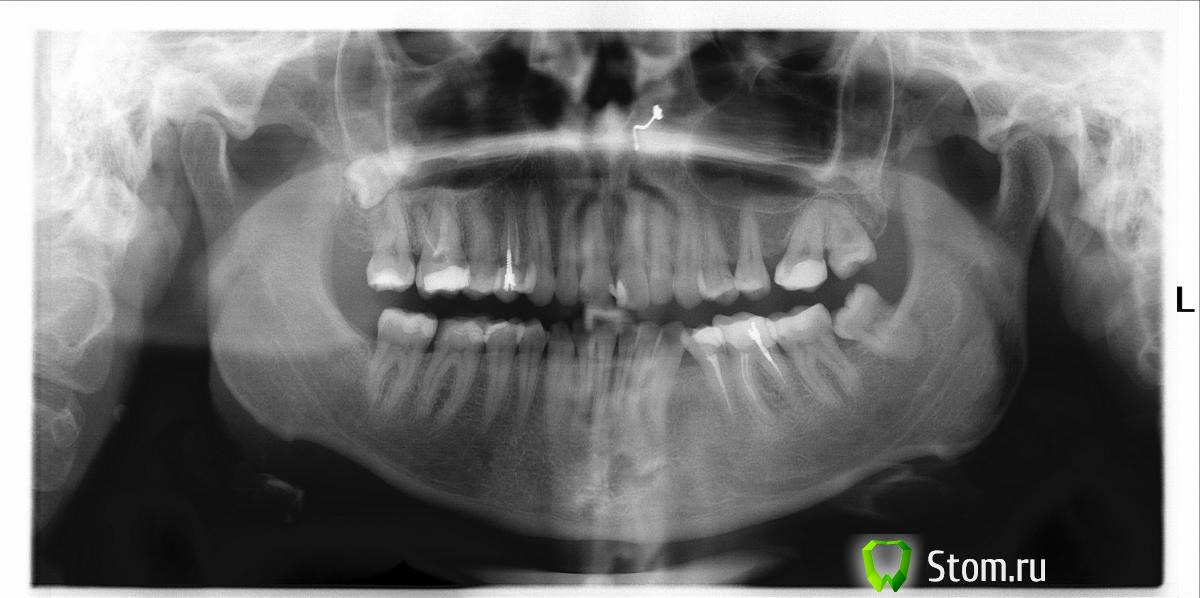

Наталия78 Опубликовано 29 января, 2012 Поделиться Опубликовано 29 января, 2012 (изменено) Здравствуйте, уважаемые стоматологи. Некоторое время назад заболела вся правая сторона челюсти. Сходила, сделала снимок. Доктор сказал: Скорее всего надо будет перелечивать каналы.... Не смогла себя заставить добровольно пойти на этот подвиг (последние несколько раз, когда лечила зубы, анестезия как-то не очень анестезировала). Несколько дней пила обезбаливающее, оно же противовосполительное. Все вроде прошло. Но проблему откладывать нельзя, все равно придется лечить. Буду очень благодарна, если вы на основании снимка сможете мне рассказать что с моими зубами, что надо будет делать и насколько все запущено.Заранее большое спасибо. Изменено 29 января, 2012 пользователем Наталия78 Ссылка на комментарий

L . O . M . Опубликовано 29 января, 2012 Поделиться Опубликовано 29 января, 2012 (изменено) Правый верх.8 - консультация хирурга , он вполне может расти и , например , "толкать" 7 зуб .6- есть воспалительный процесс . Перелечить каналы , восстановить вкладкой и коронкой .5-большая пломба . Возможен пульпит . ЭОД.14-Перелечить каналы , восстановить вкладкой и коронкой . Правый низ.7,6,5-Эод .6-очевиден вторичный кариес под пломбой , если после препарирования не "вскроется" нерв и останется достаточный объем тканей-восстановить коронковую часть зуба керамической вкладкой , если депульпация (удаление нерва) -восстановить вкладкой и коронкой . Ещё бывает гайморит , неврит . Консультации соответствующих специалистов. Простите , а что это за предмет над верхними центральными зубами ? Изменено 29 января, 2012 пользователем L . O . M . Ссылка на комментарий

ger_berra Опубликовано 30 января, 2012 Поделиться Опубликовано 30 января, 2012 Правый верх.8 - консультация хирурга , он вполне может расти и , например , "толкать" 7 зуб .6- есть воспалительный процесс . Перелечить каналы , восстановить вкладкой и коронкой .5-большая пломба . Возможен пульпит . ЭОД.14-Перелечить каналы , восстановить вкладкой и коронкой . Правый низ.7,6,5-Эод .6-очевиден вторичный кариес под пломбой , если после препарирования не "вскроется" нерв и останется достаточный объем тканей-восстановить коронковую часть зуба керамической вкладкой , если депульпация (удаление нерва) -восстановить вкладкой и коронкой . Ещё бывает гайморит , неврит . Консультации соответствующих специалистов. Простите , а что это за предмет над верхними центральными зубами ? + брекеты одеть.У Вас проблемы с прикусом. Ссылка на комментарий

Наталия78 Опубликовано 30 января, 2012 Автор Поделиться Опубликовано 30 января, 2012 Огромное спасибо всем, кто отреагировал на мою просьбу... Я, конечно, знала, что у меня не все хорошо, но чтоб настолько..... . И это только по правой стороне, а ведь есть еще и левая..... Но вот что оказалось полной неожиданностью, так это брекеты.... Возможно не очень корректный вопрос с моей стороны: если столько зубов мне надо именно переделать, это значит, что они изначально были сделаны не очень хорошо? И я очень извиняюсь: а что значит ЭОД? P.S. Предмет - пирсинг .... Ссылка на комментарий

shishok Опубликовано 30 января, 2012 Поделиться Опубликовано 30 января, 2012 ЭОД- электроодонтодиагностика(определение электровозбудимости пульпы-живой/неживой зуб) Ссылка на комментарий